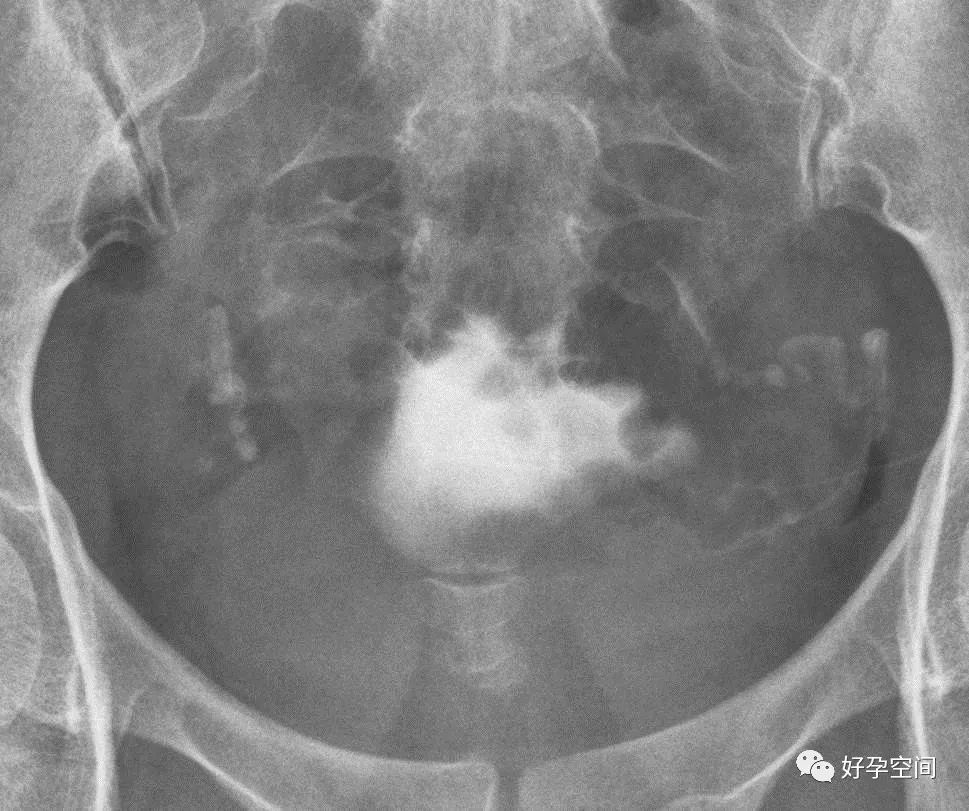

子宫相